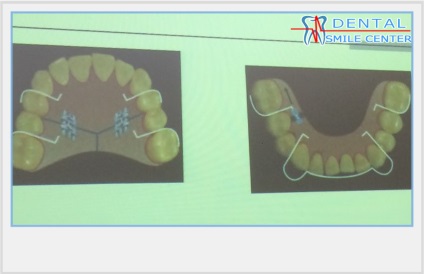

A szájüregi distaliziruschie apprat. Sok eszközök distalization zápfog. Készülékek ritkábban használtak, például a korlátozott hely a nyelvet. Nyelv nem tudja ellátni teljes funkcióját.

A fenti eszközök vannak kitéve szegmentális aktiválási, 1 alkalommal havonta. Azaz, 1 alkalommal havonta aktiváljuk az egyik oldalon, a második alkalommal - a második oldalon.